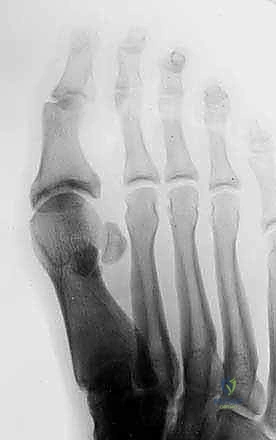

2. التصوير بالأشعة السينية (X-Rays)

يتم إجراء صور أشعة سينية بوضعيات تحمل الوزن (Weight-bearing) وبوضعيات الإجهاد (Stress views). تساعد الأشعة السينية في:

* استبعاد وجود كسور في عظام المشط أو السلاميات.

* تقييم العظام السمسمانية (البحث عن كسور أو هجرة غير طبيعية للعظام السمسمانية، مما يدل على تمزق الصفيحة).

* تقييم تضيق المسافة المفصلية.